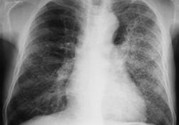

小兒肺炎的癥狀表現(xiàn)有哪些?小兒肺炎應(yīng)該怎么治療?

小兒肺炎在孩子中是很容易發(fā)生的,孩子身體免疫力比較低,容易受到傳染。那么,小兒肺炎的癥狀表現(xiàn)有哪些呢?

小兒肺炎癥狀

早期癥狀: 流清鼻涕、鼻塞、噴嚏等,也可用流淚、微咳或咽部不適,可在3~4天內(nèi)自然痊愈。開始為頻繁的剌激性干咳,隨之咽喉部出現(xiàn)痰鳴音,咳嗽時可伴有嘔吐、嗆奶。有時淋巴結(jié)可稍腫大。呼吸表淺增快,鼻扇,部份患兒口周、指甲輕度發(fā)紺。除呼吸道癥狀外伴有精神萎靡、煩躁不安、食欲不振、哆嗦、腹瀉等全身癥狀。在嬰幼兒容易引起嘔吐及腹瀉。

晚期癥狀: 持續(xù)高熱、全身中毒等癥狀嚴(yán)重,且伴有其它臟器功能損害。伴有冷感,頭痛、全身無力、食欲銳減、睡眠不安等,不久即可因部微紅,發(fā)生皰疹和潰瘍,有時紅腫明顯,波及扁桃體,出現(xiàn)濾泡性膿性滲出物,咽痛和全身癥狀均加征,鼻咽分泌物從稀薄變成粘稠。